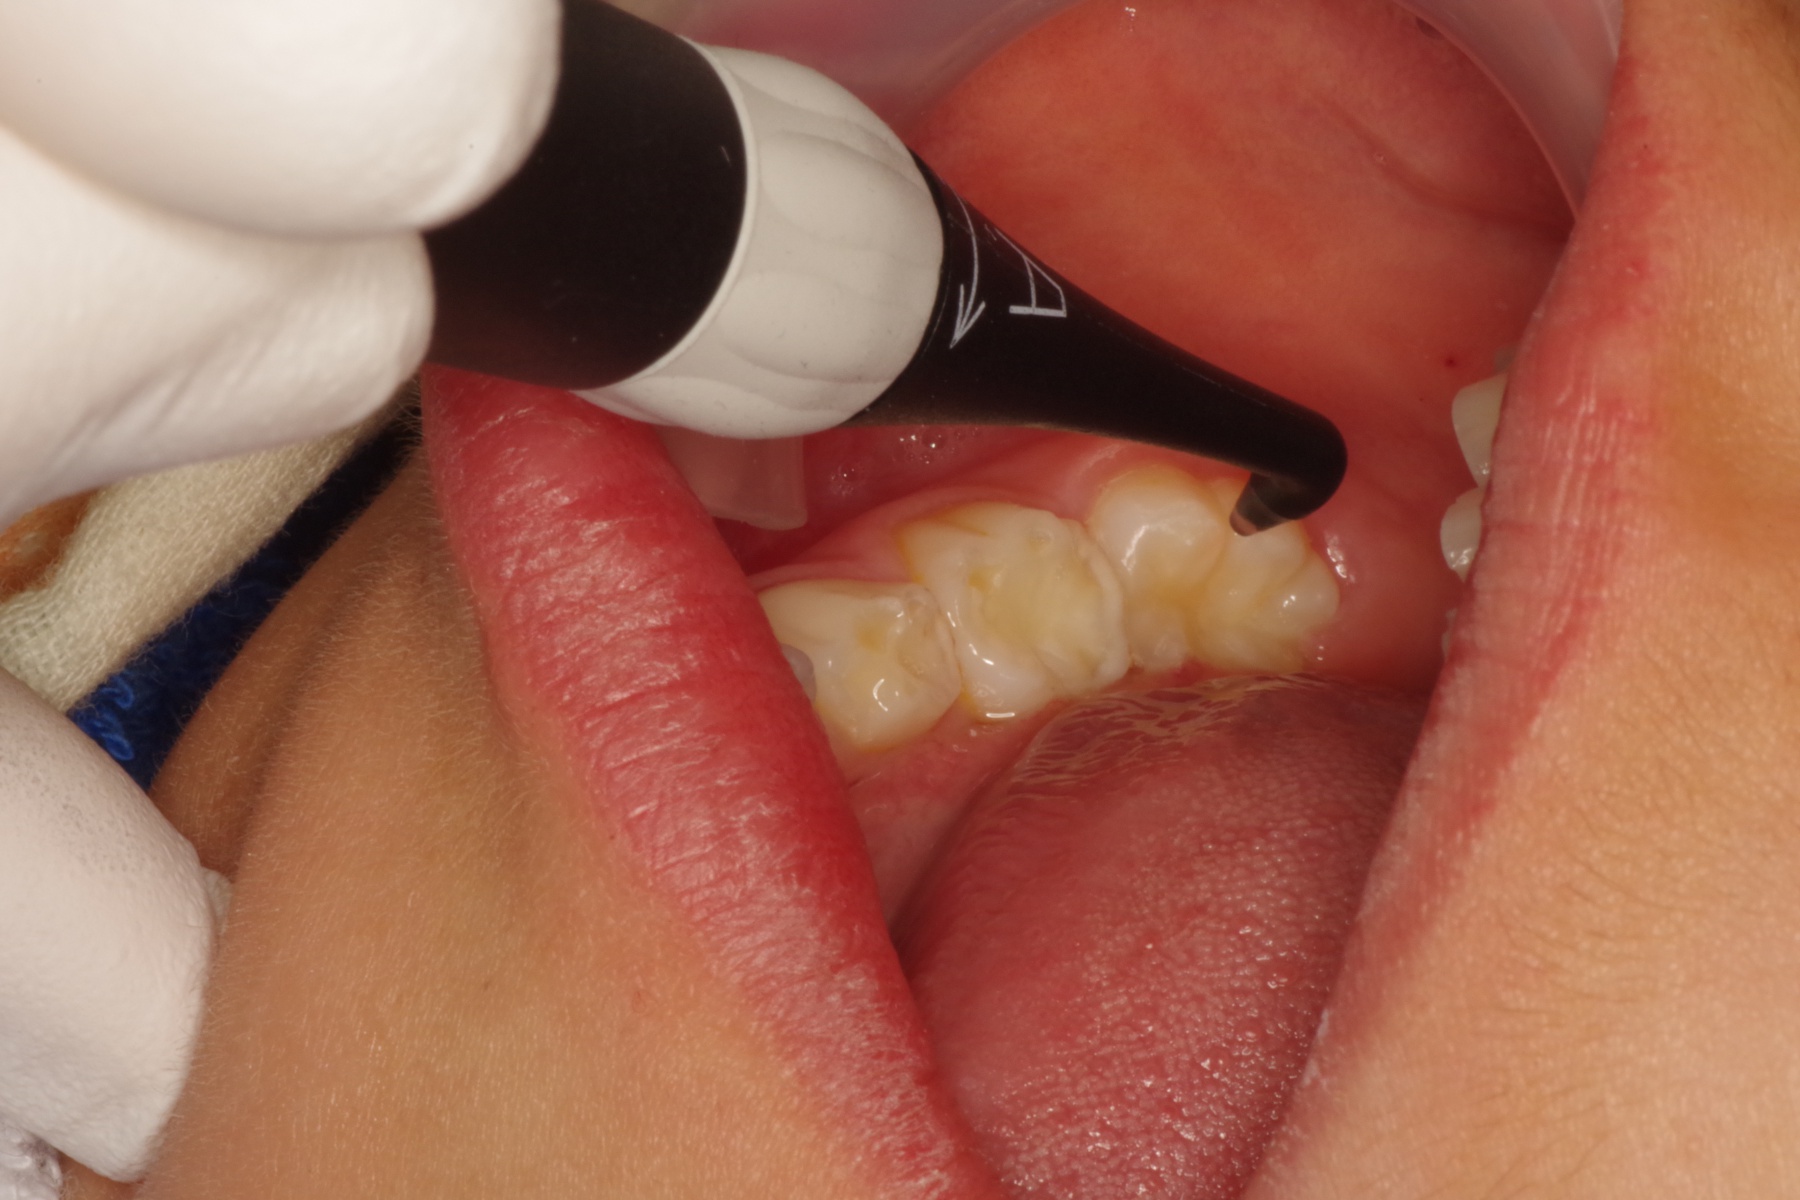

実際の視診に加え、必要に応じてレントゲン撮影や、写真のような機械を使い、虫歯の早期発見をいたします。